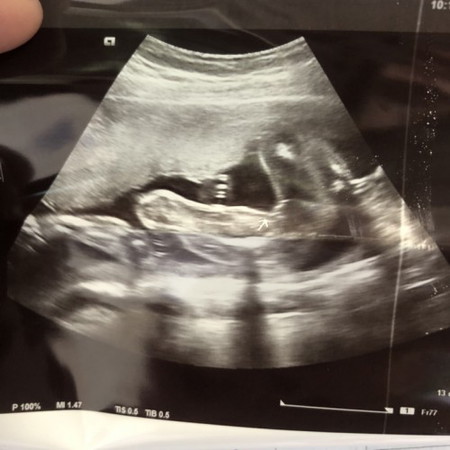

แม่ๆเห็นเป็นรุปร่างชัดมั้ยค่ะ6เดือนเเล้วน้องไม่ให้เห็นเพศเลยค้า

แม่ๆช่วยดูหน่อยค่ะ แบบนี้ผู้หญิงหรือผู้ชายค่ะ คนแรกตื่นเต้นมากๆ

น่าจะผู้หญิงนะคะเพราะไม่เห็นจุ๊ดจู๋เลยค่ะ👧🏻👧🏻

เป็นกลีบเลยแม่ เหมือนของบ้านนี้เลยค่ะ

มาเป็นกรีบเลยจ้าแม่ ผู้หญิงแน่นอนจ้า😆😊

แบบนี้ละ น้องเป็น ผู้ชาย หรือ ผู้หญิง ค้ะ

เป็นกรีบจ้า น่าจะผู้หญิงแม่

แบบนี้หญิงหรือชายคะ

น่าจะผู้หญิงนะคะ